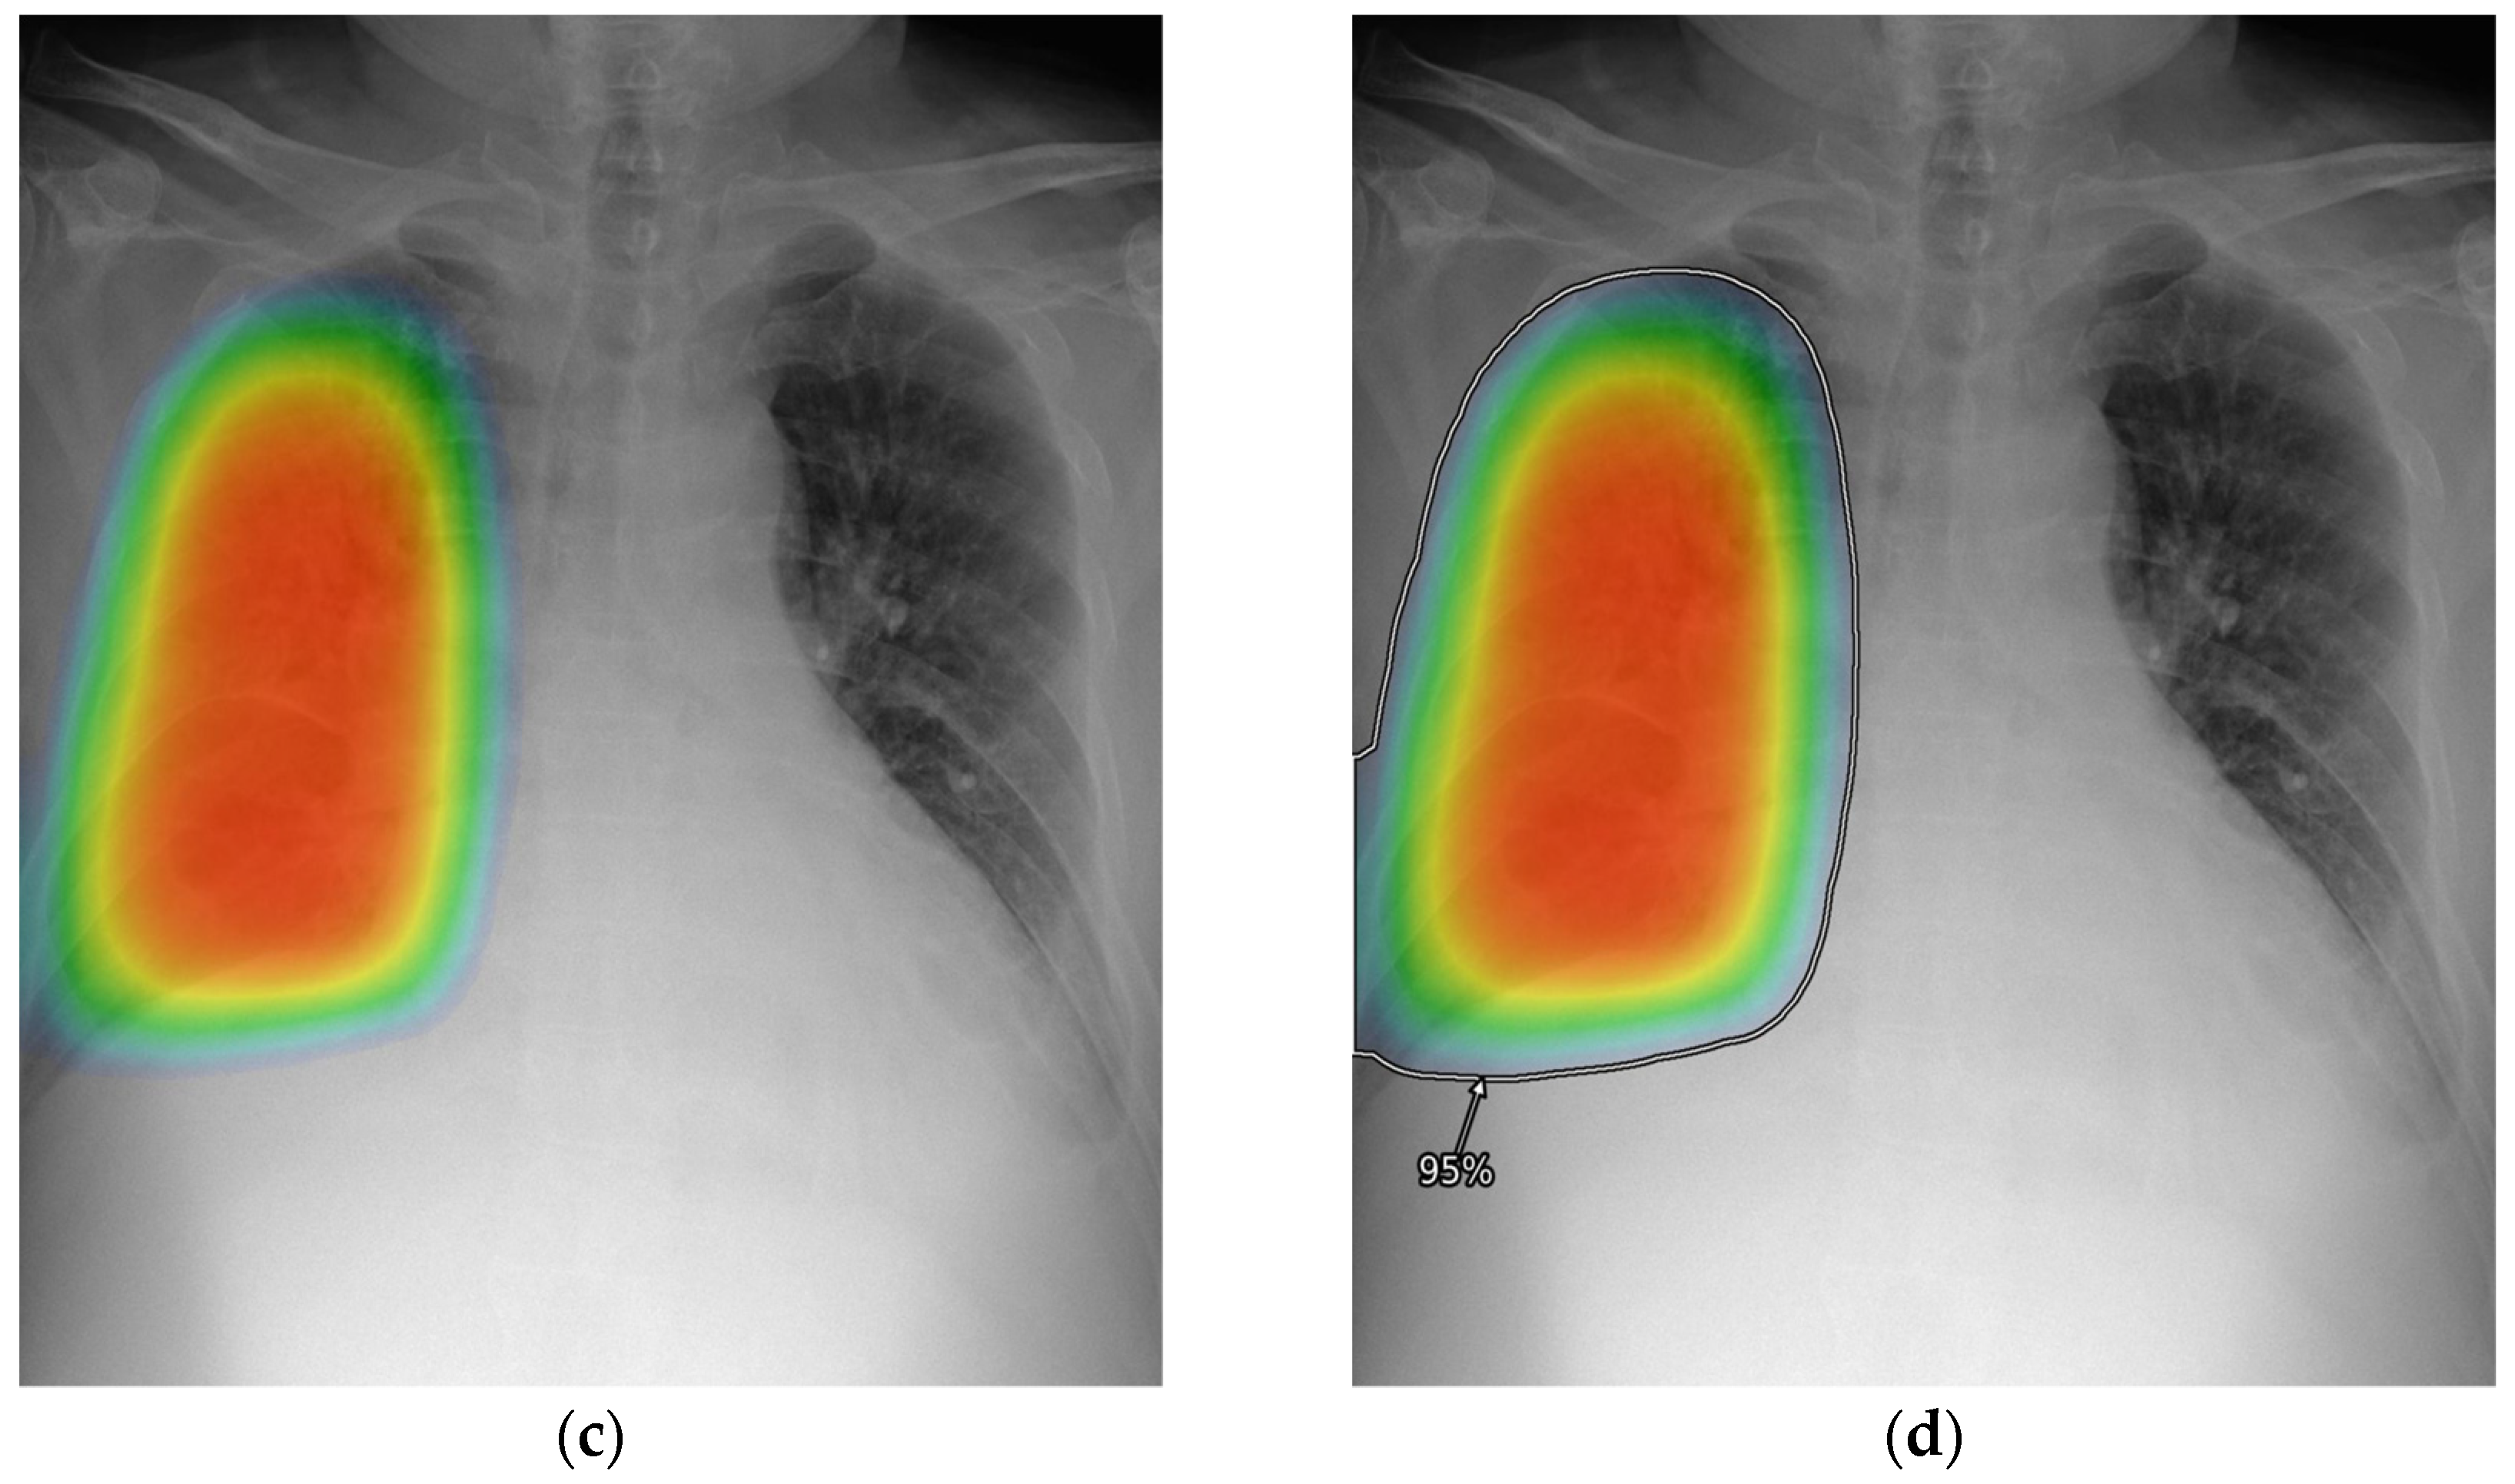

2.3. AI-CAD